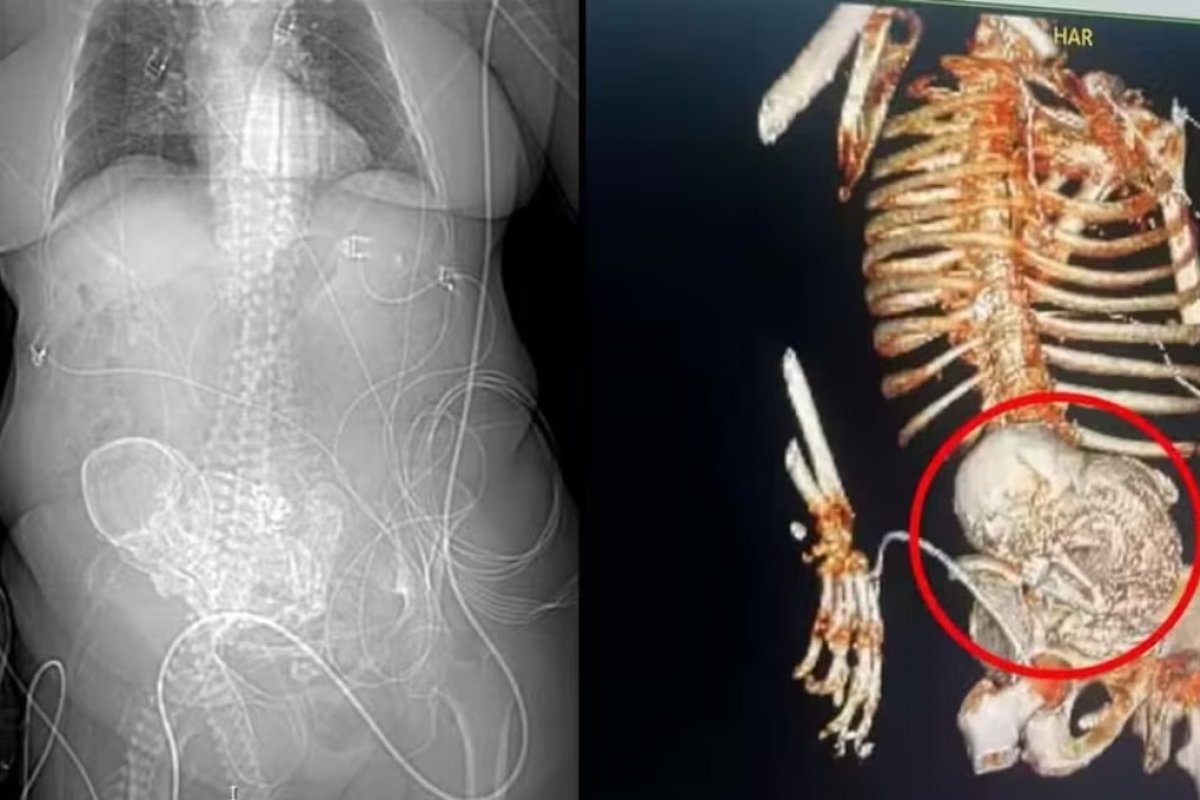

A família da indígena Daniela Almeida Vera, morta no último dia 14 de março em decorrência de uma infecção generalizada, autorizou a realização de estudos com o bebê calcificado encontrado no interior do abdômen da idosa.

Daniela foi portadora de uma condição raríssima chamada de litopedia, termo usado para descrever uma gravidez ectópica abdominal na qual o feto morre, mas não pode ser reabsorvido pelo corpo da mãe.

Em outras palavras, a condição acontece quando o óvulo fertilizado é implantado fora do útero. A gravidez ectópica sempre evolui para a morte do feto e, em casos raros, pode haver a calcificação.

Em situações assim, para proteger a mãe de uma infecção, o sistema imunológico reconhece o feto como um corpo estranho e faz uma película protetora de cálcio em torno dele.

O caso foi descoberto após a indígena dar entrada na unidade de saúde com um quadro de infecção urinária grave.

Após realizar alguns exames, foi descoberto o feto calcificado na região do abdômen da mulher, que passou por uma cirurgia para retirada do 'bebê de pedra'. Um dia após a cirurgia, a idosa não resistiu e faleceu.